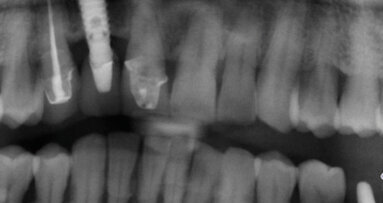

Quasi misconosciuta nella realtà, l’implantologia pterigoidea, oltre ad essere poco insegnata, è spesso confusa con altre. È in grado di risolvere immediatamente gravi carenze, ovviate in genere attraverso soluzioni economicamente più impegnative e dalla morbilità estremamente più complessa.

Intenso il dibattito sulla chirurgia guidata nella sua declinazione odontoiatrica, focalizzate le strutture anatomiche specifiche e varianti, attraverso il materiale didattico a tal fine selezionato nel tempo e messo a disposizione dell’Istituto. Materiale del resto indispensabile per conoscere la collocazione spaziale delle strutture sensibili circostanti per padroneggiare questo tipo di implantologia.